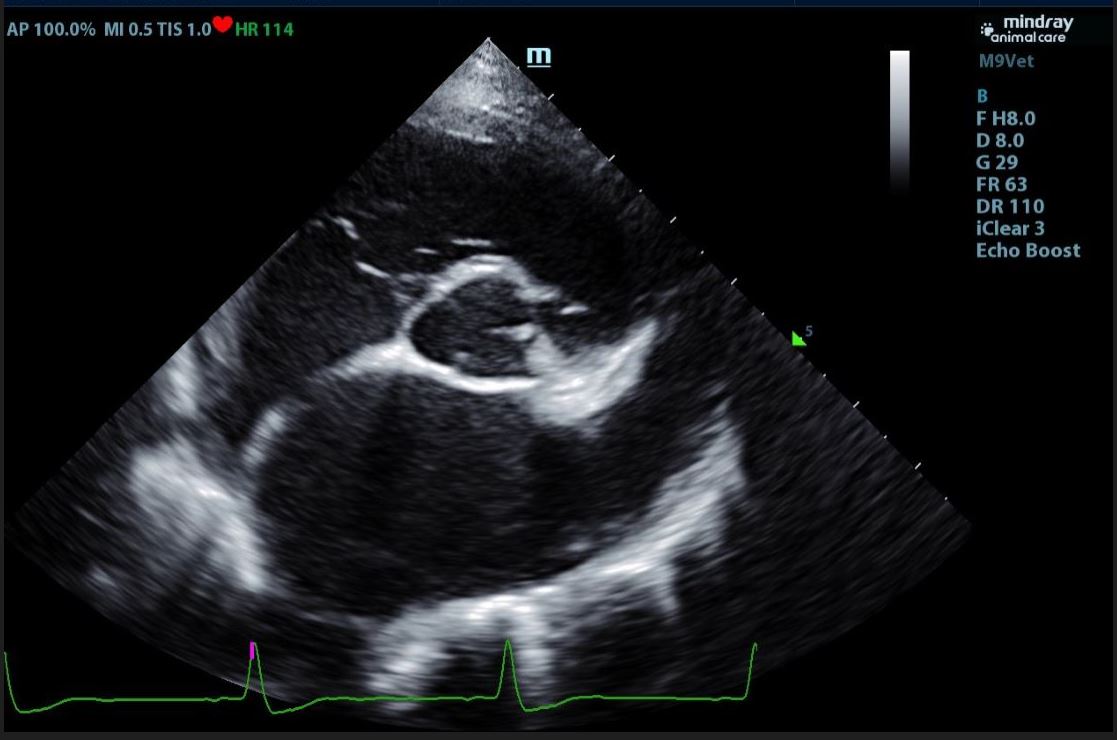

Echocardiograms

Veterinary echocardiography is a type of ultrasound imaging that focuses on the heart. Echocardiography assesses the structure and function of an animal's heart. This non-invasive procedure employs ultrasound technology to produce detailed, real-time images of the heart's chambers, valves, and blood flow. Echocardiography is essential for diagnosing and monitoring heart conditions such as heart murmurs, cardiomyopathy, and valve disorders. It helps veterinarians evaluate the severity of heart disease, guide treatment decisions, and monitor the effectiveness of therapies, all while ensuring the animal's comfort and safety.